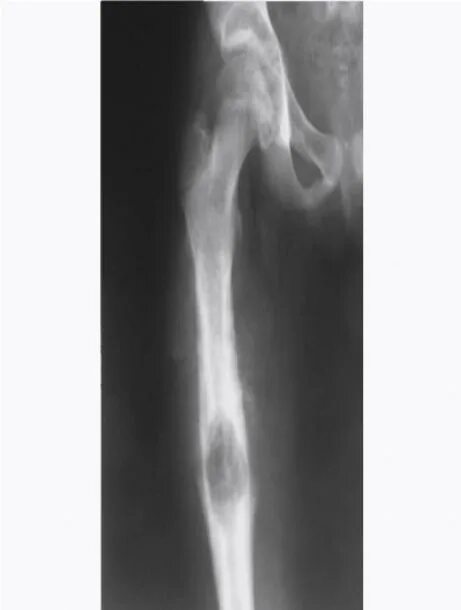

Остеосклероз суставов